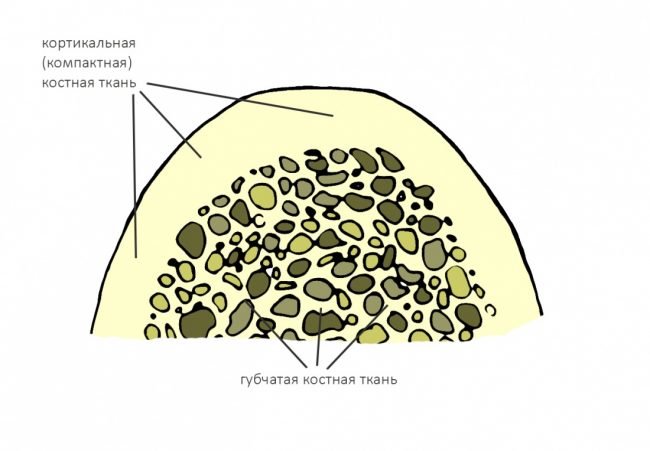

Челюстная кость, как, впрочем, любая другая, неоднородна по своей структуре. В её наружном слое, называемом кортикальной (или компактной) пластинкой, преобладает межклеточное вещество с высокой степенью минерализации. Во внутренней части, губчатом веществе, наоборот, межклеточного вещества не так уж и много, зато присутствует большое количество клеточных элементов, сосудов и нервов.

Соотношение внешней кортикальной и внутренней губчатой части челюстной кости определяет ее биотип.

В этой статье я уже рассказывал про биотипы костной ткани и том, почему это важно при планировании имплантации. Вот картинка, поясняющая, что такое биотипы, и в чём между ними разница:

Зная биотипы, удельное содержание клеточных элементов костной ткани, роль межклеточного вещества и то, как всё это влияет на регенераторные процессы, мы можем сделать интересные выводы:

- Биотипы D1 и D2 — наиболее сложные для имплантации и остеопластики, поскольку имеют выраженную кортикальную пластинку, почти не имеющую клеточных элементов, необходимых для регенерации. Это противоречит общепринятым представлениям, но именно так оно и есть. Смиритесь и отправляйтесь учить гистологию.

- Аутотрансплантация кортикальный блоков к кортикальной же костной ткани не приводит ни к чему хорошему. Отсутствие кровоснабжения у такого регенерата объясняет их резорбцию и утрату в долгосрочной перспективе. Чтобы этого не происходило, есть несколько секретов, о которых речь пойдет позже.

- То же самое касается метода направленной костной регенерации без подготовки принимающего ложа, пусть и в меньшей степени. Миграция клеток из компактной пластинки кости затруднена по причине их почти полного отсутствия. Это объясняет неудачи применения чистых биоматериалов при НКР и то, почему регенерация нуждается в дополнительных стимуляторах в виде аутокостной стружки — при её разрушении остеокластами и прочими макрофагами, образуются факторы роста, влияющие на миграцию и формирование остеобластов.